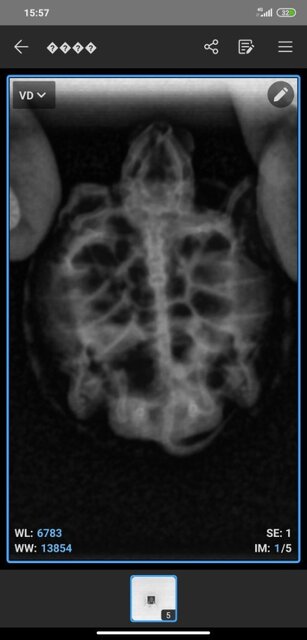

1760179420857.jpg

1760179420854.jpg

1760179420850.jpg

1760179420844.jpg

1760179381867.jpg